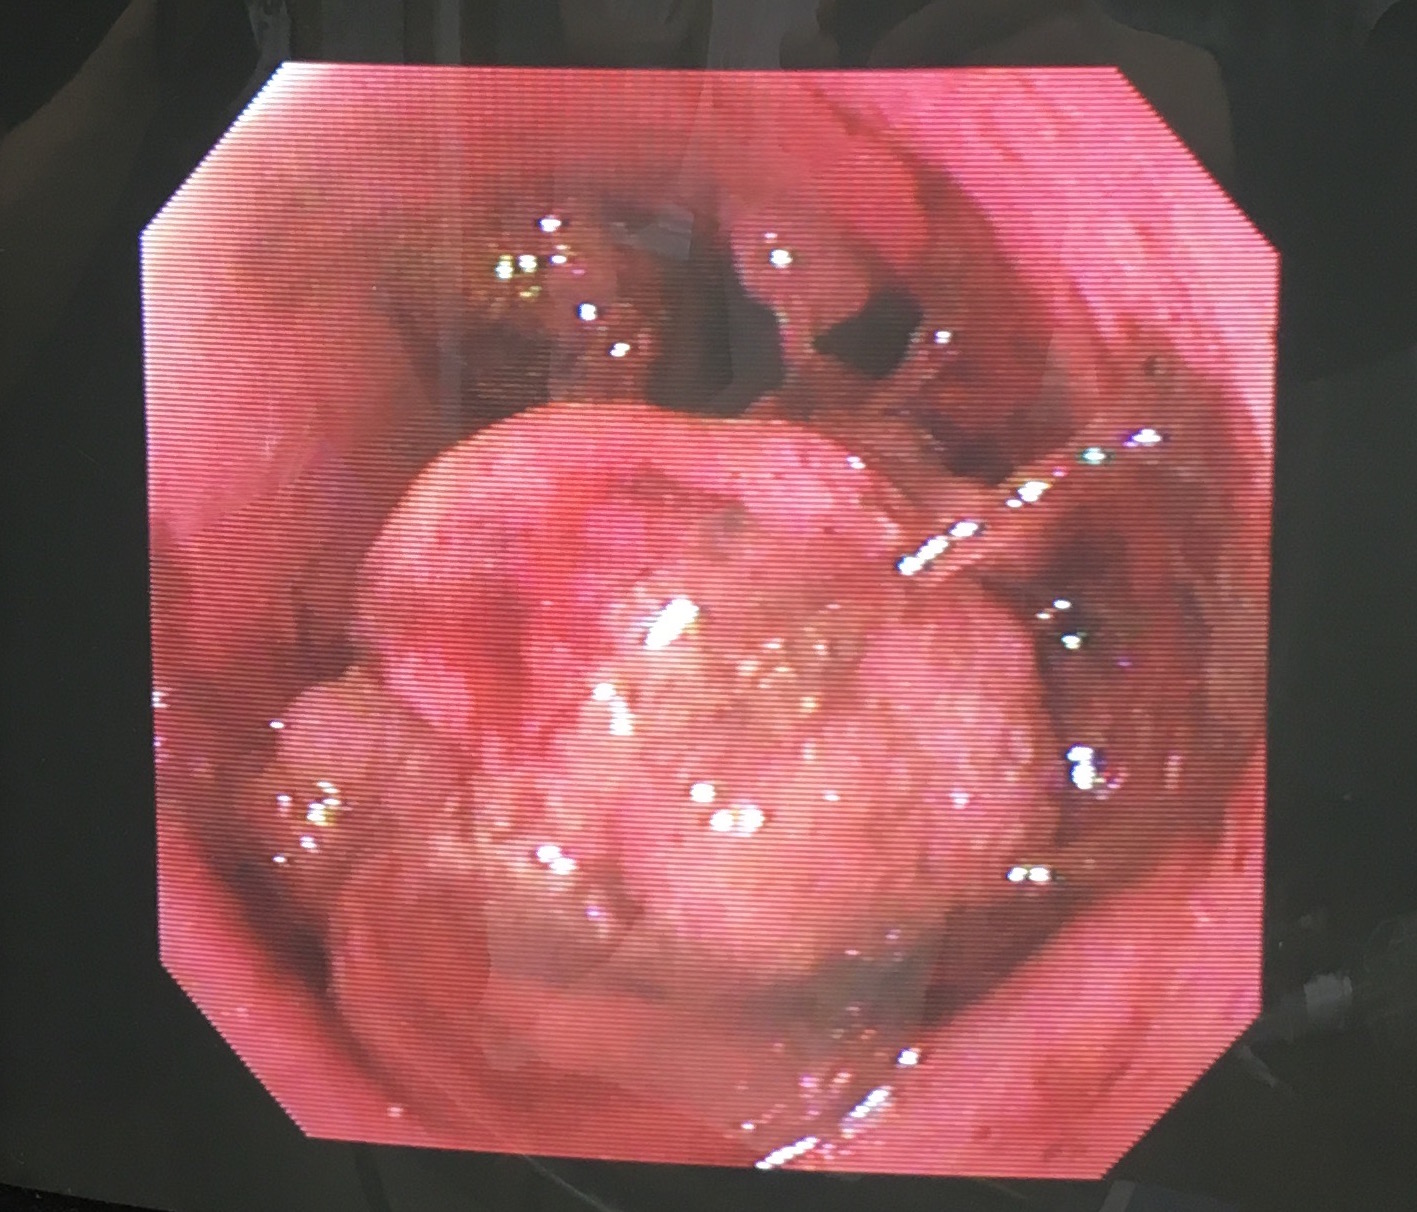

画像・写真|『週刊プレイボーイ』38号表紙(c)yorokobi/週刊プレイボーイ 2枚目 / 南里美希、シースルーまといセクシーグラビア 大人の色気直腸プルスルー法を用いて直腸切除術を行いました。 肛門から直腸を引き抜いてきて切除する術式です。 ①まずは、肛門から直腸粘膜を引きずり出します。 病変の広がりを把握するため、肛門から15cm程度離れた病変のない部位を切開します。 ②切開し 元気可愛いプルスルーブレイドアレンジ♪6 サイド&バックスタイル 画像女の子のママさん必見! 元気可愛いプルスルーブレイドアレンジ♪7 アクティブ可愛い髪型でしたよね♪ 手が込んでいる分、とっても豪華ですね! 子供も喜ぶこと

![]() 犬の大腸癌の手術法 新千歳動物病院のブログ | ![]() 犬の大腸癌の手術法 新千歳動物病院のブログ | ![]() 犬の大腸癌の手術法 新千歳動物病院のブログ |

犬の大腸癌の手術法 新千歳動物病院のブログ | 犬の大腸癌の手術法 新千歳動物病院のブログ | ![]() 犬の大腸癌の手術法 新千歳動物病院のブログ |

犬の大腸癌の手術法 新千歳動物病院のブログ | ![]() 犬の大腸癌の手術法 新千歳動物病院のブログ | ![]() 犬の大腸癌の手術法 新千歳動物病院のブログ |